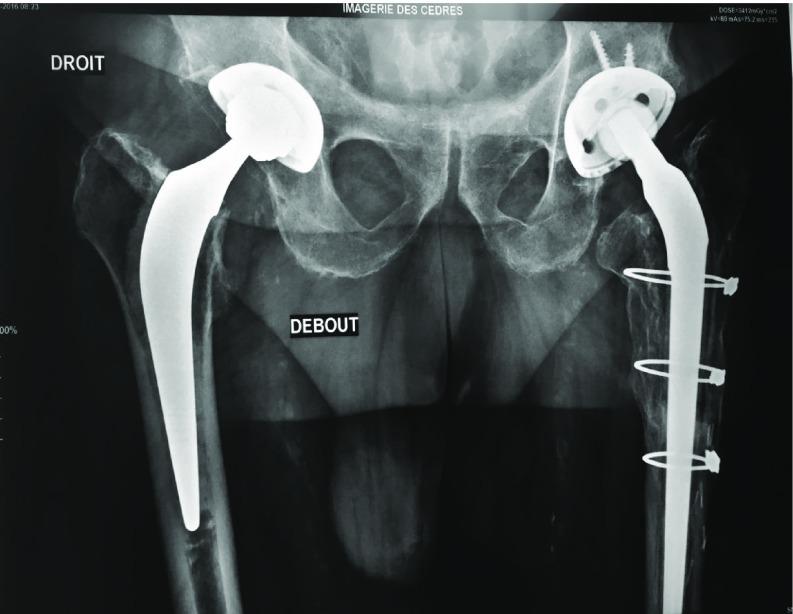

The trans femoral osteotomy was initially described by Wagner in 1987 and the extended trochanteric osteotomy (ETO) was described by Younger et al. in 1995 and is considered to be the gold standard technique for removal of well-fixed femoral stems in revision total hip arthroplasty (THA). The purpose of this report is: to compare the different types of fixation metallic wires, cables, metallic reinforcement plate (MRP) we have used in revision THA where an ETO was performed; analyse the clinical and radiological outcomes of these devices at 1 year; analyse the complication.

It is a retrospective continuous monocentric series of 157 patients where an ETO was performed. It was fixed by an MRP in 17 patients, cables in 43, metallic wires in 97. The main outcome was the consolidation of the osteotomized femoral flap (OFF). Secondary outcomes were Postel Merle d'Aubigne score and complications occurred at 1 year follow up. Qualitative variable was presented as percentage, quantitative variables as mean or median, standard deviation and range.

157 patients (73-46, 5% females) were included. Mean age at surgery was 66.7 year (sd = 10.63). Mean interval between index surgery and revision was 11.07 year (sd = 5.67). Causes for revision and bone defects were comparable. At 1 year OFF is healed without displacement in 82% with metallic wires, 70% with cables, 88% with MRP. Not significant.

经股骨截骨术最初由瓦格纳于1987年描述,而扩大转子截骨术(ETO)由扬格等人于1995年描述,被认为是翻修全髋关节置换术(THA)中取出固定良好的股骨柄的金标准技术。本报告的目的是:比较我们在进行ETO的翻修THA中使用的不同类型的固定金属丝、缆线、金属加强板(MRP);分析这些装置在1年时的临床和放射学结果;分析并发症。

这是一项回顾性连续单中心系列研究,共纳入157例行ETO的患者。其中17例用MRP固定,43例用缆线固定,97例用金属丝固定。主要结局是截骨股骨瓣(OFF)的愈合。次要结局是术后1年的Postel Merle d'Aubigne评分和并发症。定性变量以百分比表示,定量变量以均值或中位数、标准差和范围表示。

纳入157例患者(73例男性,46例女性,5%为女性)。手术时的平均年龄为66.7岁(标准差=10.63)。初次手术与翻修之间的平均间隔时间为11.07年(标准差=5.67)。翻修原因和骨缺损情况具有可比性。1年后,使用金属丝固定的患者中82%的OFF愈合且无移位,使用缆线固定的为70%,使用MRP固定的为88%。差异无统计学意义。